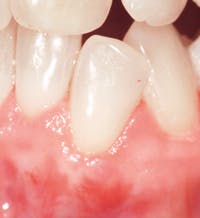

In our ongoing efforts to provide patients with the best standard of care, there are many products that are used to help the clinician, hygienist, and patient obtain optimal results. Straumann Emdogain when combined with a coronally advanced flap (CAF) is one such product. This product is a biology-based and scientifically proven solution designed to promote predictable regeneration of hard and soft tissues lost to periodontal disease for a natural-looking result.

Without the use of Emdogain, the periodontist performs a "periodontal plastic surgery" procedure in which connective tissue taken from the patient's palate is used to cover the exposed root. With the use of Emdogain, patients tend to have less pain and discomfort because there is no need for a second surgical site.5 Straumann Emdogain is designed to promote the regeneration of hard and soft tissues that anchor your teeth. When patients learn this, treatment compliance increases.

Emdogain is designed to reverse recession naturally. How? In much the same way stem cells work to generate new cell growth, Emdogain uses proteins - which the body produces naturally - to regenerate lost gum tissue, bone, and the structures that anchor teeth to bone.6